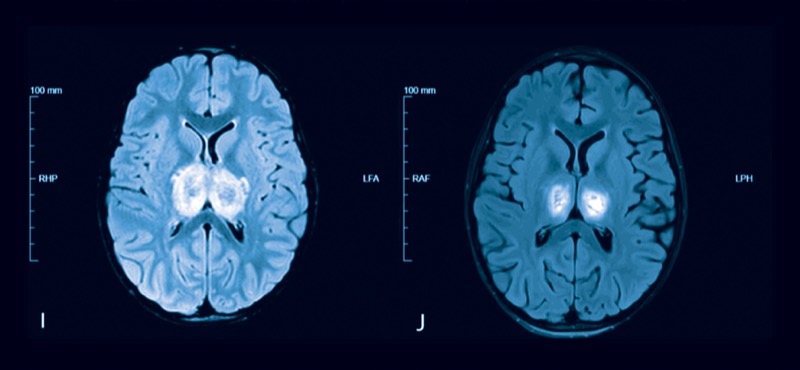

As of Feb. 8, 2025, IAE was identified in nine of 68 children who had influenza and died. This includes four children who were diagnosed with acute necrotizing encephalopathy (ANE) (MMWR Morb Mortal Wkly Rep 2025;74[6]:91-95).

All of the ANE deaths occurred in children younger than 5 years of age with laboratory-confirmed influenza A(H1N1)pdm09, one of whom had underlying medical conditions.